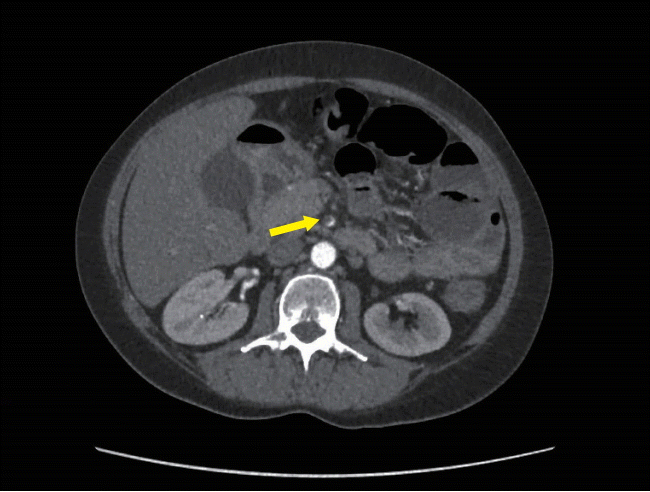

An initial CT scan of the abdomen and pelvis did not show any evidence of colitis or bowel obstruction. However, the spleen was heterogenous and showed features consistent with splenic infarction (Fig. 3).

Fig. 3.

Abdominal CT finding. CT of the abdomen demonstrates area of infarction within the spleen (arrow).